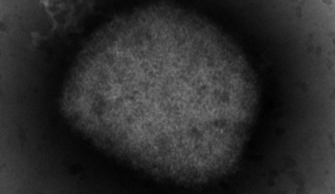

Monkeypox: Canada’s top doctor urges those at risk to get vaccinated as cases climbMonkeypox, which causes flu-like symptoms and skin lesions, is transmitted to humans from animals caused by an orthopoxvirus, which is related to smallpox, according to PHAC.CanadaJul 27, 2022